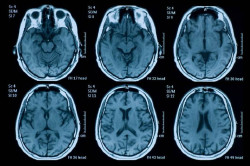

Identifican un compuesto con un efecto neuroprotector "significativo" en traumatismo craneoencefálico

Un equipo de investigadores internacionales liderados por la compañía Aivocode, una `spin-off` del institudo Sanford Burnham Prebys de San Diego (Estados Unidos), ha identificado un "significativo" efecto neuroprotector del compuesto CAQK en modelos de ratón y cerdo de traumatismo craneoencefálico.